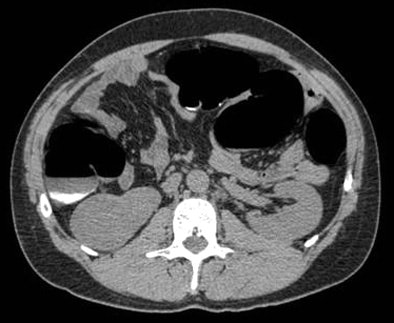

| A 52-year-old asymptomatic male underwent screening virtual colonoscopy with completly negative results in the colon. Examining the kidneys, the radiologist found a 5-cm mass that was later diagnosed as renal cell carcinoma. Image courtesy of Dr. Mark Klein. |

Of course radiologists aren't looking for insignificant findings, but rather "large lesions for which you can actualy make a difference," Klein said. These include worrisome renal masses, aortic aneurysms, solitary pulmonary nodules, lymphadenopathy, indeterminate renal masses, hydronephrosis, lesions of diffuse liver disease, and bone lesions.